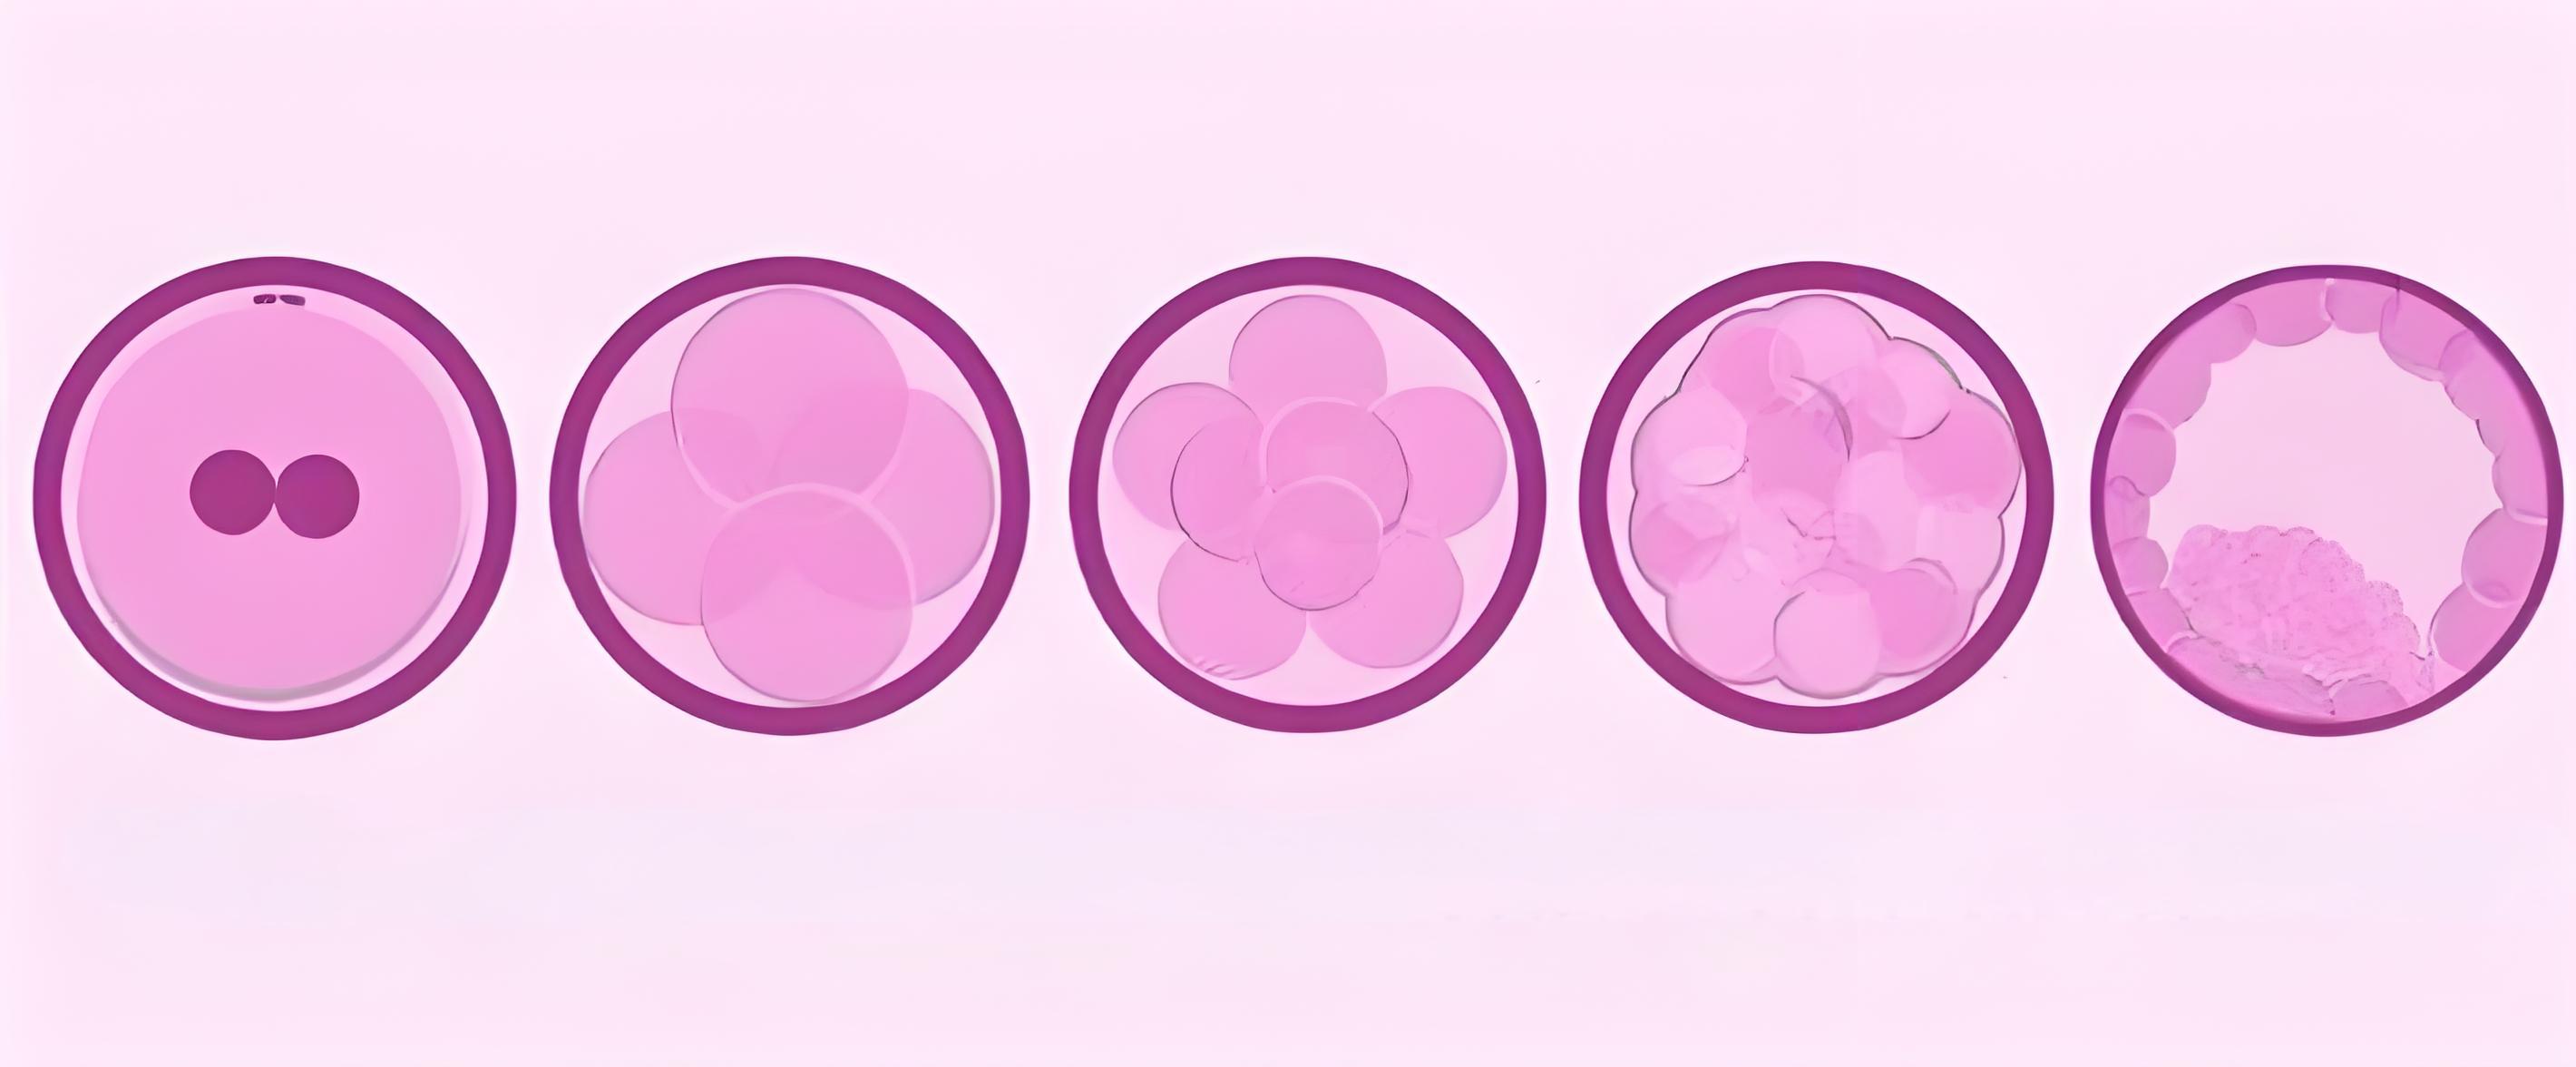

4、囊胚培育

泰国试管婴儿机构-Fertility生殖医疗集团独立拥有4所经美国的CLIA和CAP认证的尖端胚胎实验室,其中的胚泡培养箱可模拟人体的宫内环境,使受精卵在温度、湿度、含氧量、PH值等与子宫内环境一致的环境中生长发育。

HRC专家根据女性子宫分泌的营养物质,专门研制出囊胚培养所需的优质培养液。在养囊过程中,专家也会及时更新培养皿中的培养液,确保囊胚能够顺利生长发育。

将受精卵放入培养皿培养后,第2~3天,受精卵会经过卵裂,分裂成由几个至十几个细胞组成的实心细胞团,形成早期的胚胎。第4天胚胎将发育形成桑葚胚,随后进入高速分裂期,细胞加倍分裂、增长,第5天就会分裂成由一百多个细胞组成的囊胚。